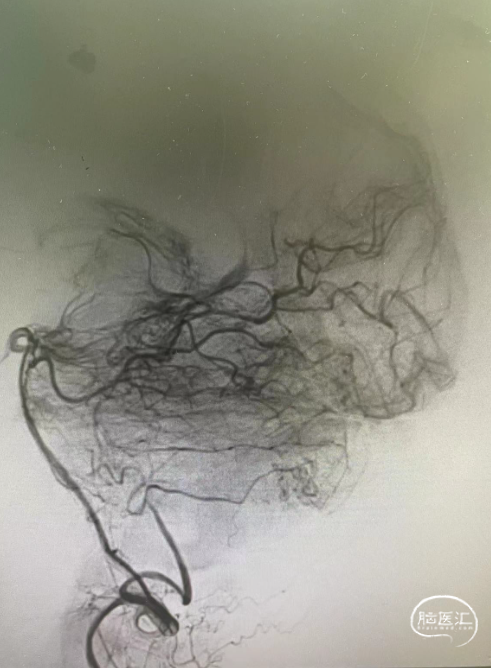

第三台,一个侧窦区的硬脑膜动静脉瘘,供血动脉繁多,以前的栓塞让脑膜中动脉的路径给用掉了。

颈内动脉脑膜垂体干有供血。

栓塞路径都不好,枕动脉供血动脉里面挑选出一支,经过努力,很好的到达了瘘口。

接着的事情就是往里面打栓塞剂。

继续打,直到将瘘口完全闭塞。

再次造影,那些繁杂的血管消失了,瘘口得到了很好的解决。